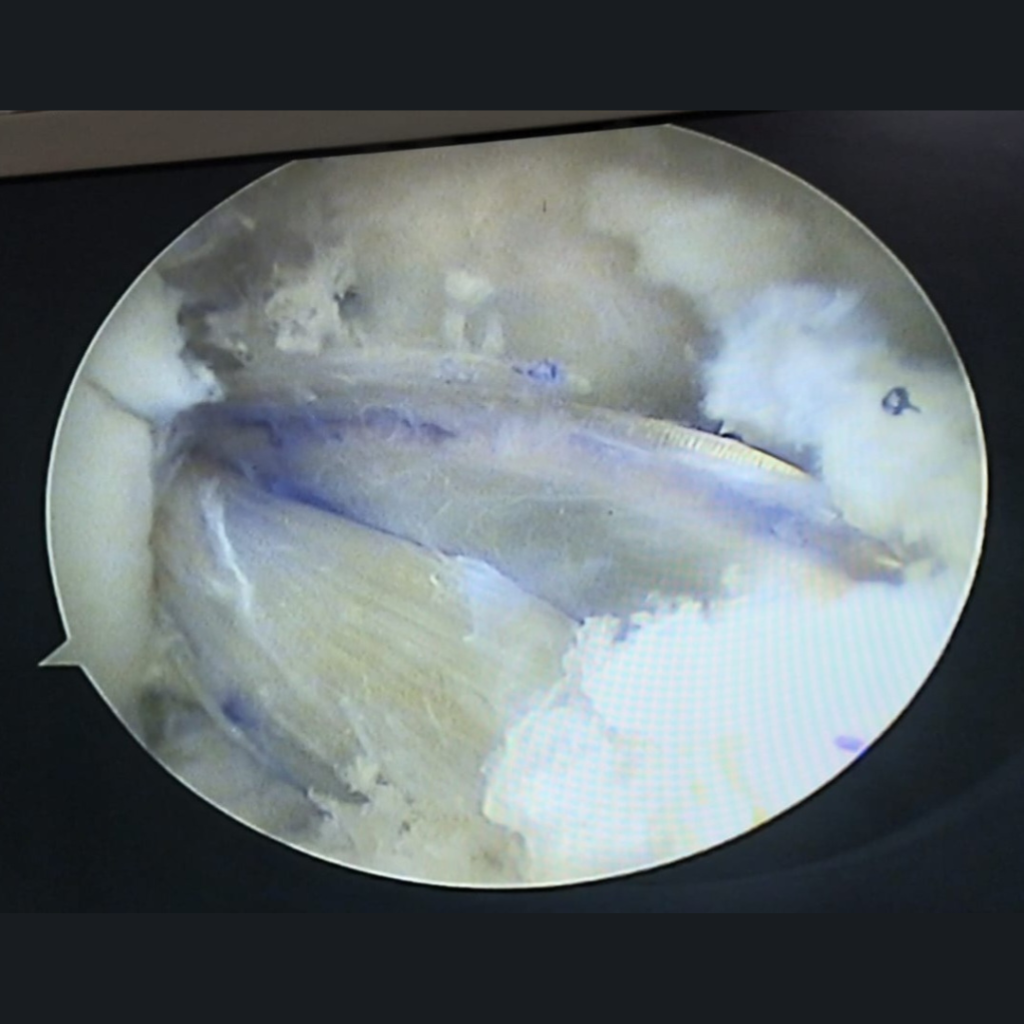

Arthroscopy is a procedure for diagnosing and treating joint problems. A surgeon inserts a narrow tube attached to a fiber-optic video camera through a small incision — about the size of a buttonhole. The view inside your joint is transmitted to a high-definition video monitor.

Arthroscopy allows the surgeon to see inside your joint without making a large incision. Surgeons can even repair some types of joint damage during arthroscopy, with pencil-thin surgical instruments inserted through additional small incisions.

• Damaged or torn cartilage

• Torn ligaments

ACL RECONSTRUCTION